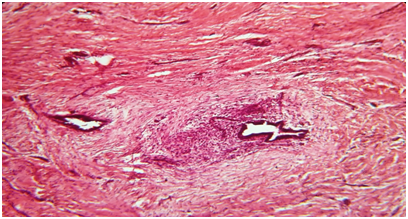

28 years old P2L2female patient reported to Gynecology department with a painful swelling at left angle of previous LSCS pfannenstiel scar for 6 years. She delivered her first Full term Alive and Healthy baby by LSCS 6 years back. She first felt pain at operated site 3 months after the surgery. It was cyclic and used to subside without any treatment. About 3 years back, she again conceived and delivered Full term, Alive and Healthy baby by LSCS. Now she presents with a tender swelling measuring 4x3x2cm at left angle of healed pfannenstiel scar. It was well circumscribed, firm and situated in subcutaneous plane. Rest of her systemic examination, vital parameters, laboratory investigations and sonographic examination were unremarkable without any evidence of pelvic endometriosios (Figure 1). Ultrasonogram (USG) of swelling showed well defined lesion measuring 2.6x1.5.x.15cm in left pelvic region at the pfannenstiel scar site which was predominantly hypoechoic with areas of hyeprechogenecity within. Based on USG findings along with clinical history, a diagnosis of Scar endomerisois was made. Patient was taken up for wide local excision of swelling with surrounding margins of 1 cm. Gross examination of excised tissue revealed irregular, grayish black fibro fatty mass with areas of congestion and hemorrhage. Histopathology examination revealed endometrial glands surrounded by endometrial stroma, embedded in fibro collagenous tissue and hemosiderin pigment at places without any evidence of malignancy (Figure 2). All histopathology findings were consistent with Scar endometriosis. On follow up period for 6 months, she did not report for any recurrence of swelling and was completely relived of her cyclic symptoms.

Figure 2 Photomicrograph showing benign endometrial glands and stroma surrounded by fibrous scar tissue consistent with Endometriosis (Hematoxylin and eosin x200).